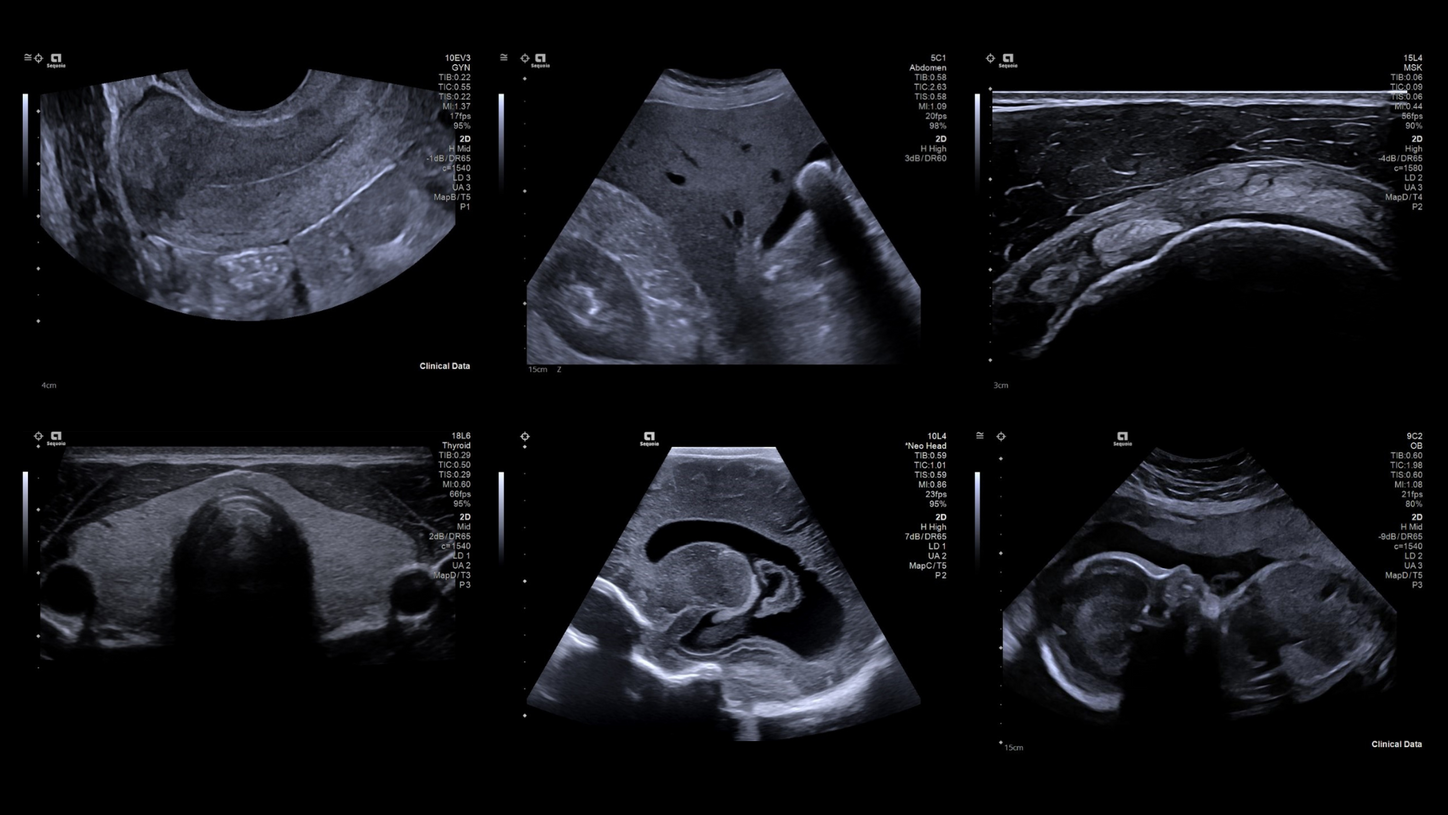

The ACUSON Sequoia is an advanced diagnostic tool that integrates cutting-edge technology and AI-powered applications to streamline diagnostic processes. This system is designed to cater to patient-specific needs, ensuring accuracy and efficiency in various clinical settings such as Radiology, OB/GYN, Shared Service and beyond.

The latest updates on ACUSON Sequoia use the power of groundbreaking AI for abdominal cases, includes advanced breast visualization to deliver new levels of image quality confidence, and tackles the toughest challenges in musculoskeletal imaging, all while saving your team from needless strain and pain.

ACUSON Sequoia’s new advanced features are designed to improve diagnostic confidence and workflow across a wide range of clinical settings.

ACUSON Sequoia’s InFocus imaging architecture eliminates the need for conventional focal zones to create a fully focused image faster than conventional systems. Our InFocus technology applies to all imaging transducers and exam types giving you consistent imaging across clinical segments. Some of the benefits are:

- Image uniformity throughout the field of view

- Aesthetically pleasing speckle

- Improved spatial and contrast resolution

- Clear near field to far field

- High resolution imaging at high frame rates

A clearer, deeper perspective with optimal acoustics for each clinical use case. Expand your assessment with advanced tools that take ultrasound beyond its traditional role.

- AI Abdomen automatically recognizes and labels 17 anatomical views and 12 routine measurements.